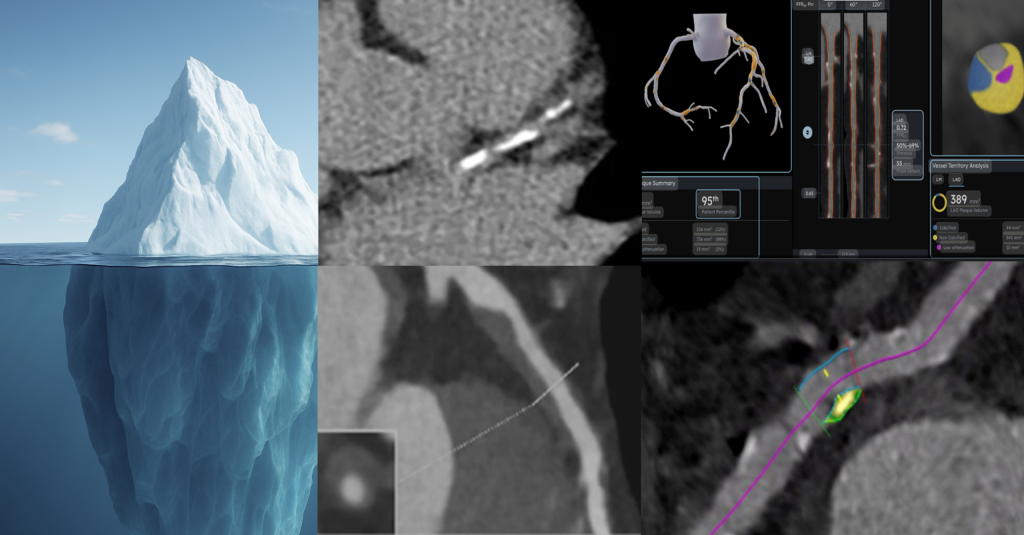

Like an iceberg, the most dangerous part of heart disease often lies beneath the surface. Traditional tests may miss soft plaque hidden buildup that increases risk without warning.

Preventi AI uses advanced AI plaque quantification to uncover what’s unseen, giving you and your doctor a clearer, deeper picture of your heart health.”

Precise Plaque Identification

Don’t guess, know. Preventi AI spots both hard and soft plaque and flags high-risk features in your coronary arteries. It brings clarity where traditional scans fall short.

Quantitative Analysis

We measure plaque the way doctors stage cancer, by type and amount. This lets us map your heart disease stage accurately and track how it changes over time.

The system evaluates plaque presence, composition, and distribution across coronary segments, generating a structured, reproducible output that surfaces disease often missed by traditional risk stratification or calcium scoring alone.

- Quantitative assessment of coronary plaque burden

- Characterization of plaque composition (calcified, non-calcified, mixed)

- Segment-level analysis aligned with coronary anatomy

- Clear visual outputs designed for clinical review